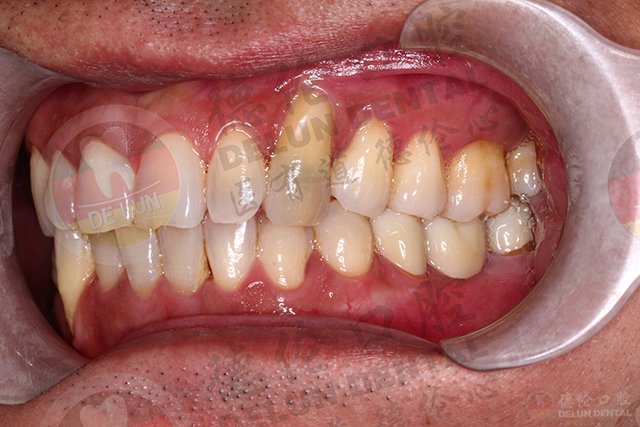

牙周炎在牙周病中常见,主要表现有牙龈红肿出血,牙周袋形成、牙周袋溢脓、牙齿松动、牙龈退缩、牙周脓肿等。牙周炎以形成病理性牙周袋为主要病变。

牙龈和牙槽骨骨组织的退缩性病变,表现为牙龈退缩,牙颈部或牙根暴露。发生牙周萎缩的主要原因是:牙颈部牙结石对牙龈的压迫;该部位牙的长期废用或全身性因素所致;不正确的刷牙方法带来的机械性刺激;修复体压迫牙龈等。查看更多德伦口腔牙周病治疗案例>>>

牙周病会引起牙龈和下方牙槽骨的退缩,引起牙间本应由牙龈和牙槽骨占据的空间暴露出来,使患者感觉牙缝越来越大。

牙齿松动移位

牙齿松动就是炎症严重的表现,有时松动可能不很明显,比如门牙缝变大了、门牙发生了扭转、门牙往外龇等等,这些都是牙周炎的症状。